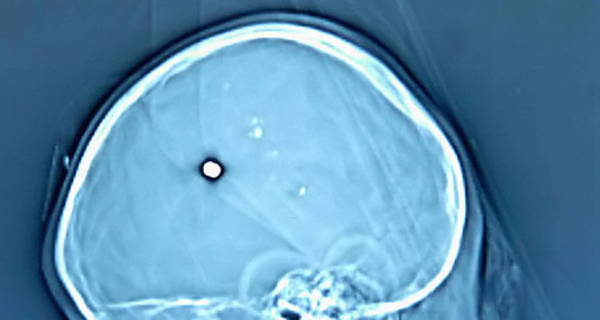

Policija u njemačkome gradu Bochumu u utorak je priopćila da su liječnici u

potiljku muškarca koji je došao odstraniti cistu pronašli metak kalibra .22.

Rana je poslije zacijelila oko metka i tek kad je zbog povremenih bolova

otišao pregledati kvrgu, saznao je što mu je u glavi.